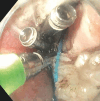

Background and study aims: Gastroesophageal reflux (GERD) can occur in a significant number of achalasia patients undergoing post-peroral endoscopic myotomy (POEM). POEM with endoscopic fundoplication (POEM-F) is a new endoscopic technique to treat post- POEM GERD. We conducted a multicenter cohort study to compare outcomes between POEM and POEM-F.

Patients and methods: We included patients who underwent POEM or POEM-F from six tertiary centers. Primary outcomes were: 1) clinical success, defined as post-procedure cessation or reduction of proton-pump inhibitors; 2) post procedure percent time pH < 4 and DeMeester score; and 3) post-procedure Eckardt scores. Secondary outcomes included adverse events, procedure time, and hospital stay duration.

Results: Sixty-four patients were included: 31 patients underwent POEM-F (mean age 51, 48% male), whereas 33 patients POEM (mean age 56, 58% male). Technical success was 100% in both groups. POEM-F patients achieved reduction/cessation in proton pump inhibitor use in 25 of 31 patients (80%); POEM patients in eight of 33 (24%) ( P ≤ 0.00001). Percent time with pH < 4 was significantly lower in the POEM-F group (2.75 +/- 2.53 vs 9.3 +/- 3.6 min, P ≤ 0.0001). Post-procedure DeMeester scores were lower (< 14.7) in POEM-F (mean 9.6) than POEM (mean 15.8) ( P ≤ 0.0011). There were three mucosal injuries in the POEM-F group and four in the POEM group. Hospital stay duration and procedure time did not differ between groups. In the POEM group, four patients required Dor fundoplication. No repeat interventions were recommended for the POEM- F group at 6-month follow-up.

Conclusions: POEM-F achieves statistically significant improvement in post- POEM GERD compared with POEM alone.